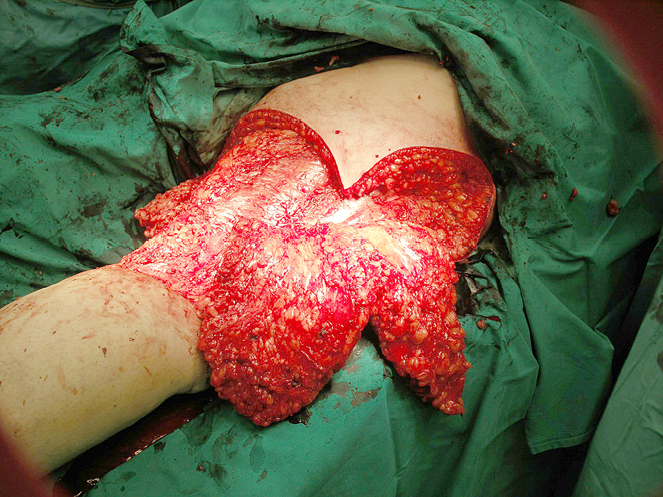

Po pakinklio odos, poodžio ir dalies fascijos ekscizijos nusiuntus odos ir žaizdos kraštų preparatus biopsijai, gautas atsakymas, jog auglio augimo nenustatyta.

Toliau operacija tęsta pagal numatytą planą: atpreparuotas ir pakeltas odos dviskiltis lopas (žr. 3A pav.). Pirmąja lopo skiltimi padengta recipientinė vieta, ji fiksuota 3/0 rezorbuojančiomis siūlėmis. Dengiant didesnės skilties paėmimo vietą, mažesne skiltimi padengta proksimaliau defekto susidariusi žaizda. Donorinė vieta susiūta be didesnio tempimo pirmine siūle, naudojant poodžio 3/0 besirezorbuojantį siūlą. Oda papildomai fiksuota metalinėmis kabutėmis. Drenai nenaudoti, nes kraujavimas buvo kruopščiai stabdomas visos operacijos metu, naudojant monopoliarinę diatermokoaguliaciją.

3A pav. Ekscizuotas melanomos recidyvas ir atpreparuotas dviskiltis lopas prieš transpoziciją